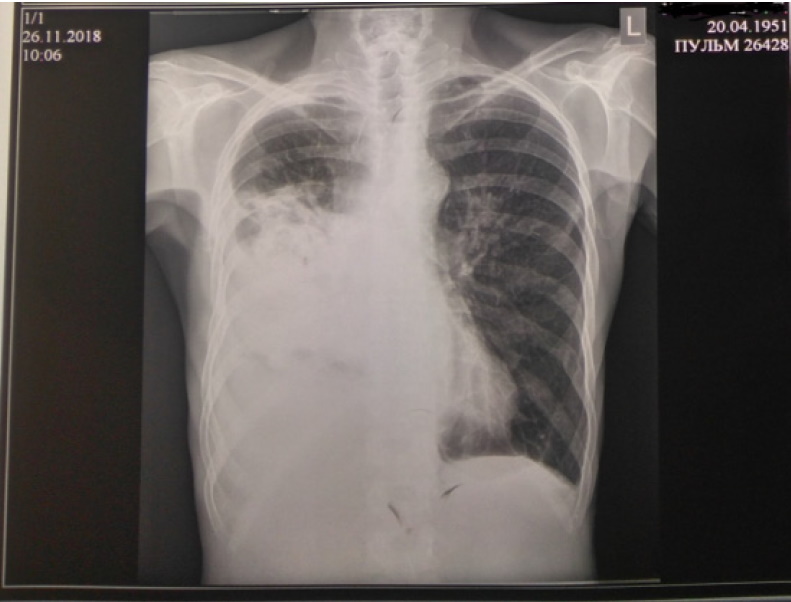

Рентгенография органов грудной клетки (ОГК) от 10.11.2018: легкие эмфизематозны справа в среднем поле, в проекции S6 снижена прозрачность за счет инфильтрации с полостями деструкции и с вовлечением прилежащей плевры, в плевральной полости жидкость с косым уровнем по переднему отрезку 5-го ребра. Левое легкое без инфильтративных изменений, парамедиастинально на уровне 4-го межреберья визуализируется плотная очаговая тень 10×15 мм с довольно четким контуром. Легочный рисунок деформирован за счет явлений пневмосклероза (рис. 2).

Рис. 2. Рентгенограмма органов грудной клетки от 10.11.2018 (позитив)